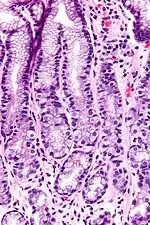

A G cell or gastrin cell is a type of cell in the stomach and duodenum that secretes gastrin. It works in conjunction with gastric chief cells and parietal cells. G cells are found deep within the pyloric glands of the stomach antrum, and occasionally in the pancreas[1] and duodenum. The vagus nerve innervates the G cells. Gastrin-releasing peptide is released by the post-ganglionic fibers of the vagus nerve onto G cells during parasympathetic stimulation. The peptide hormone bombesin also stimulates gastrin from G cells. Gastrin-releasing peptide, as well as the presence of amino acids in the stomach, stimulates the release of gastrin from the G cells. Gastrin stimulates enterochromaffin-like cells to secrete histamine.[2] Gastrin also targets parietal cells by increasing the amount of histamine and the direct stimulation by gastrin, causing the parietal cells to increase HCl secretion in the stomach. G-cells frequently express PD-L1 during homeostasis which protects them from Helicobacter pylori-induced immune destruction [3]

G cells have a distinctive microscopic appearance that allows one to separate them from other cells in the gastric antrum; their nuclei are centrally located in the cell. They are found in the middle portion of the gastric glands.